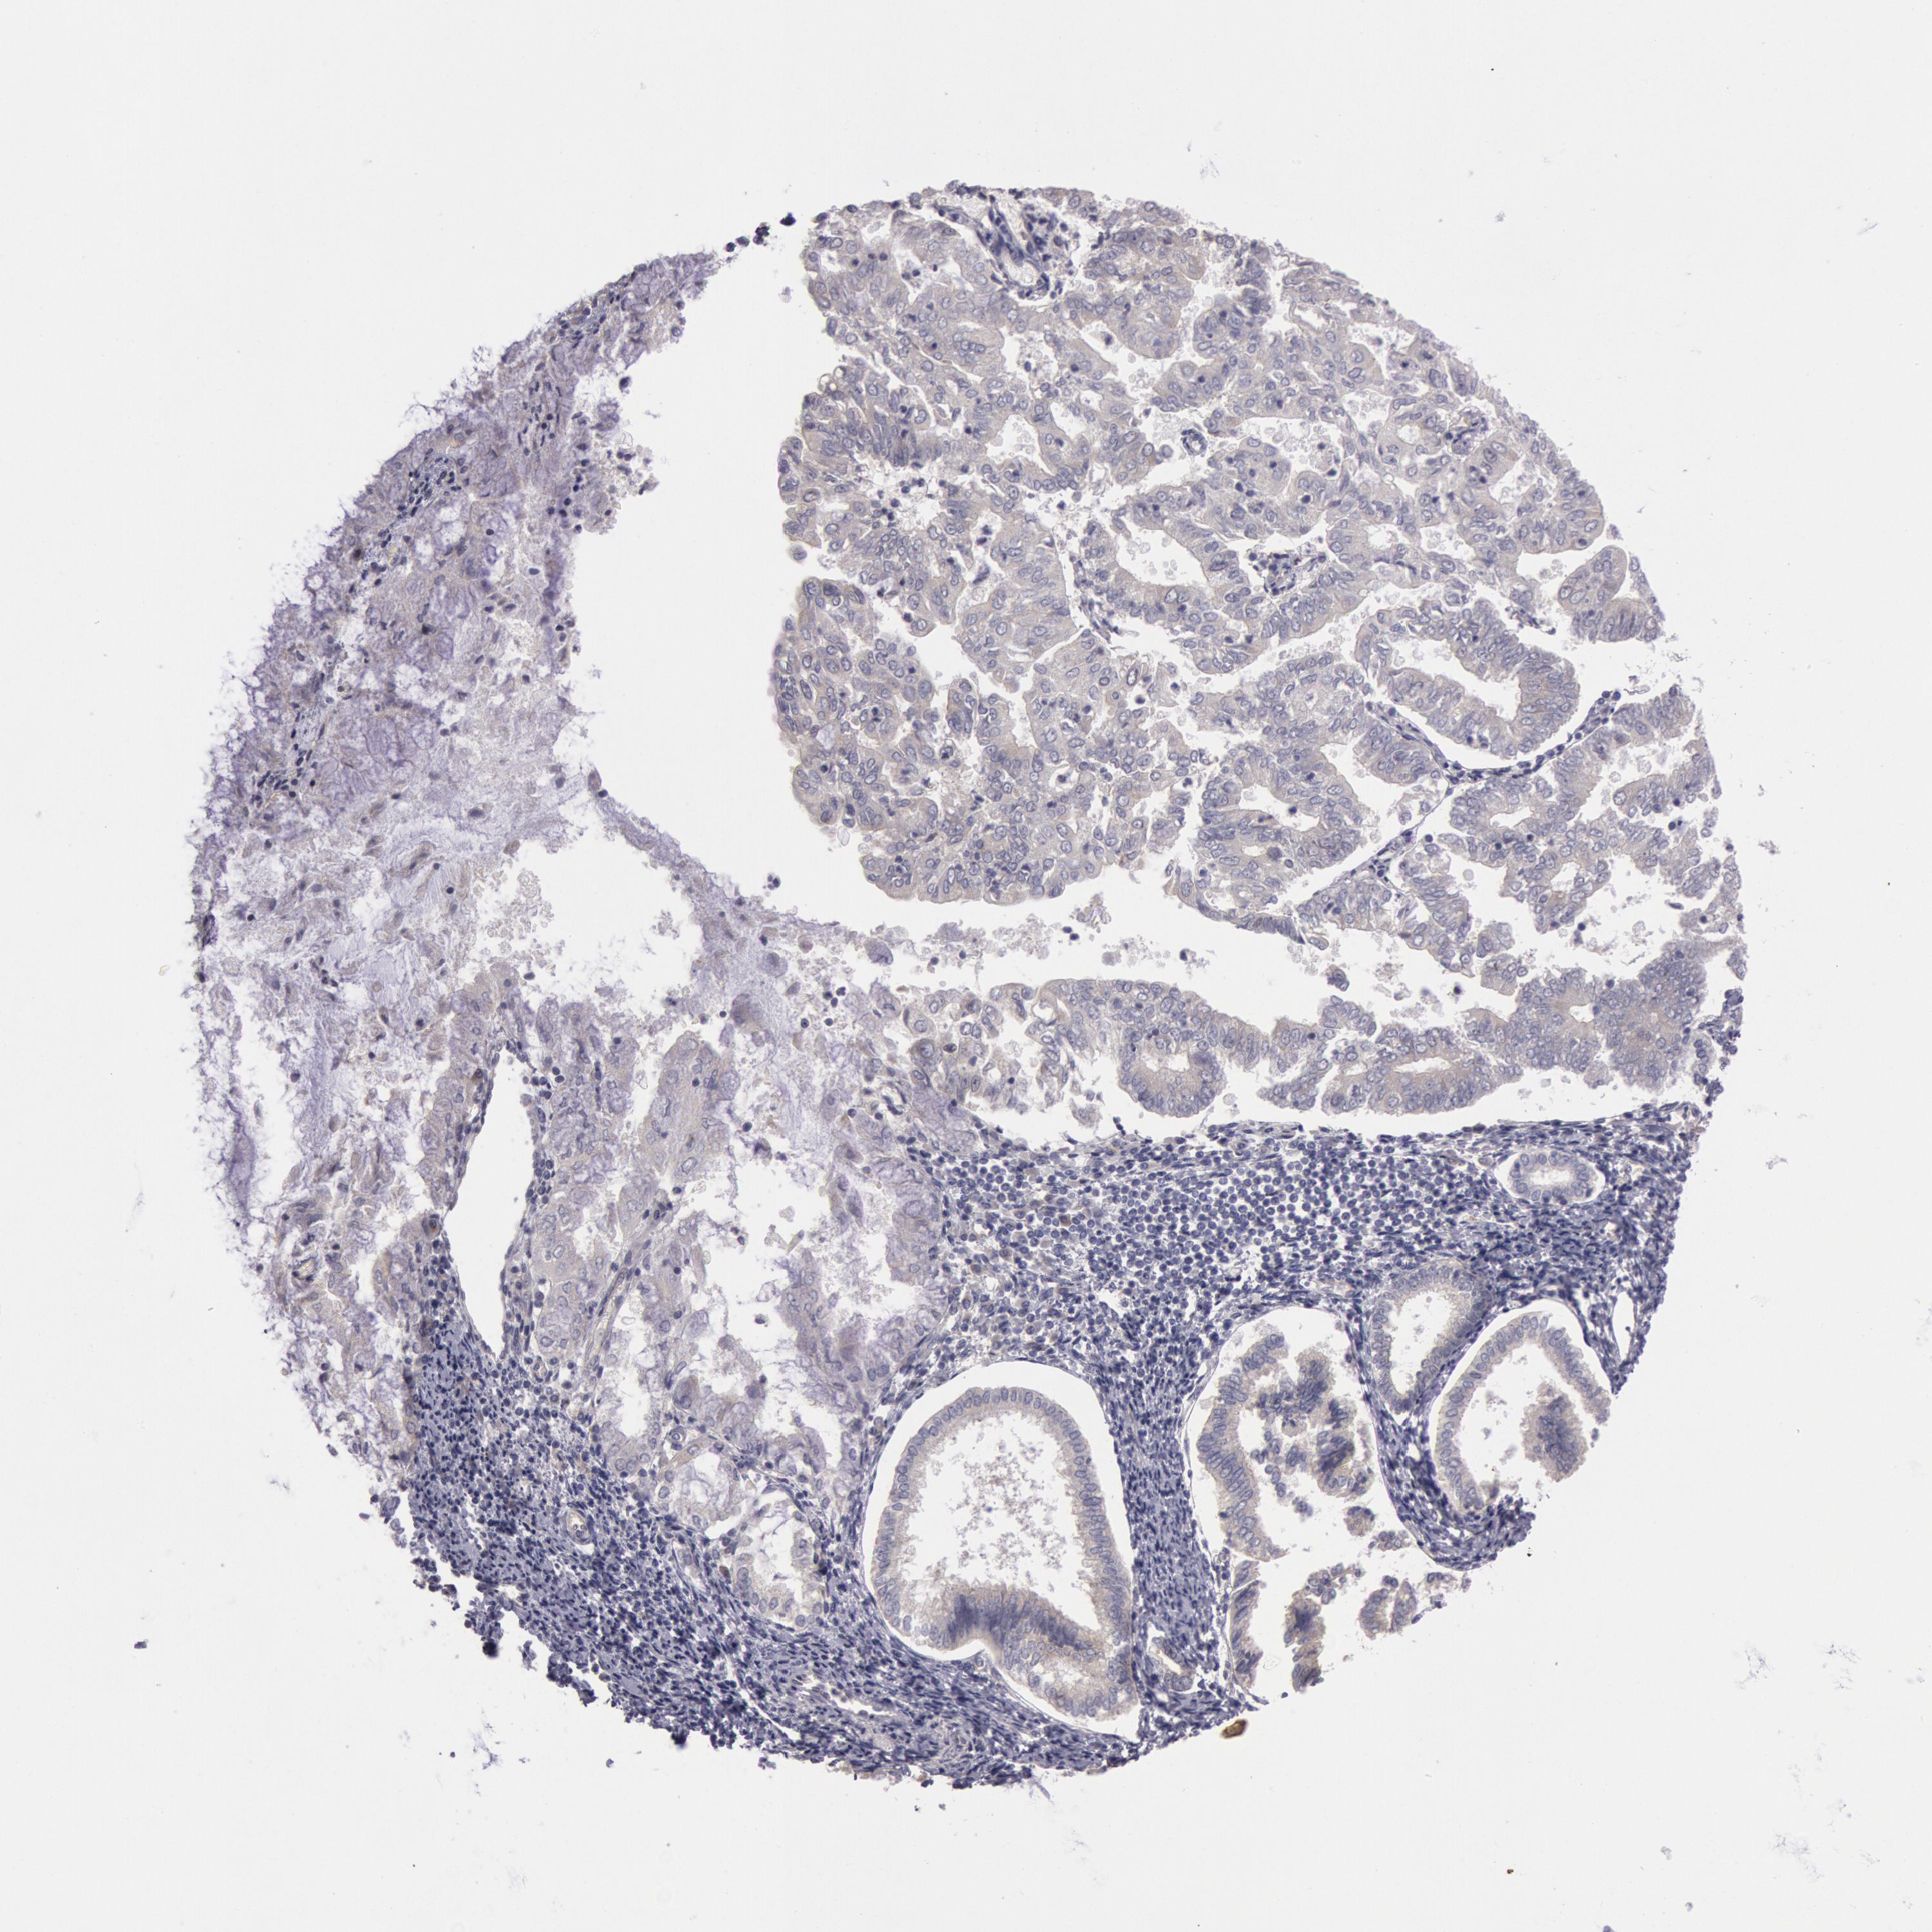

ENDOMETRIAL CANCER - Protein expressioni

A mouse-over function shows sample information and annotation data. Click on an image to view it in a full screen mode. Samples can be filtered based on level of antibody staining by selecting one or several of the following categories: high, medium, low and not detected. The assay and annotation is described here.

Note that samples used for immunohistochemistry by the Human Protein Atlas do not correspond to samples in the TCGA dataset.

Antibody stainingi

Antibody staining in the annotated cell types in the current human tissue is reported as not detected, low, medium, or high, based on conventional immunohistochemistry profiling in selected tissues. This score is based on the combination of the staining intensity and fraction of stained cells.

Each image is clickable and will lead to virtual microscopy that enables deeper exploration of all samples and also displays staining intensity scores, fraction scores and subcellular localization as well as patient and tissue information for each sample.

Antibody HPA001196

Staining

High

Medium

Low

Not detected

Intensity

Strong

Moderate

Weak

Negative

Quantity

>75%

75%-25%

<25%

None

Location

Nuclear

Cytoplasmic/membranous

Cytoplasmic/membranous,nuclear

Adenocarcinoma, NOS